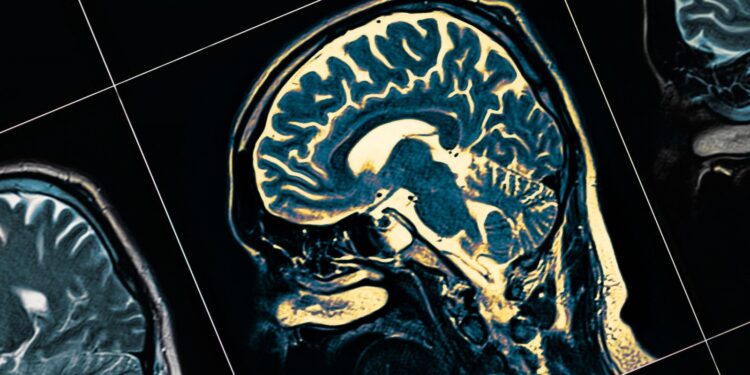

Eğer UPS arızalıysa, nöronlar "çöp kutularına" atılırken, yeni sentezlenen (bellek) ve yeni uzun süreli belleklerin oluşturulması için gerekli olan kullanılmış proteinler arasındaki denge bozuluyor ve sinir bağlantılarının kaybına (sinaptik başarısızlık) yol açan hafıza proteinlerinin eksikliği oluşuyor. Bu hasar başlangıçta beynin yeni anıların oluşması için hayati önemi olan bölümü olan hipokampusta meydana geliyor. Nöronlar ölürken beynin diğer kısımları da etkileniyor.